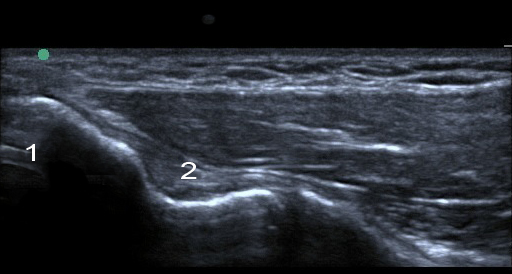

Imagen del ligamento colateral cubital del codo

Epitróclea

Ligamento colateral cubital (LCC)